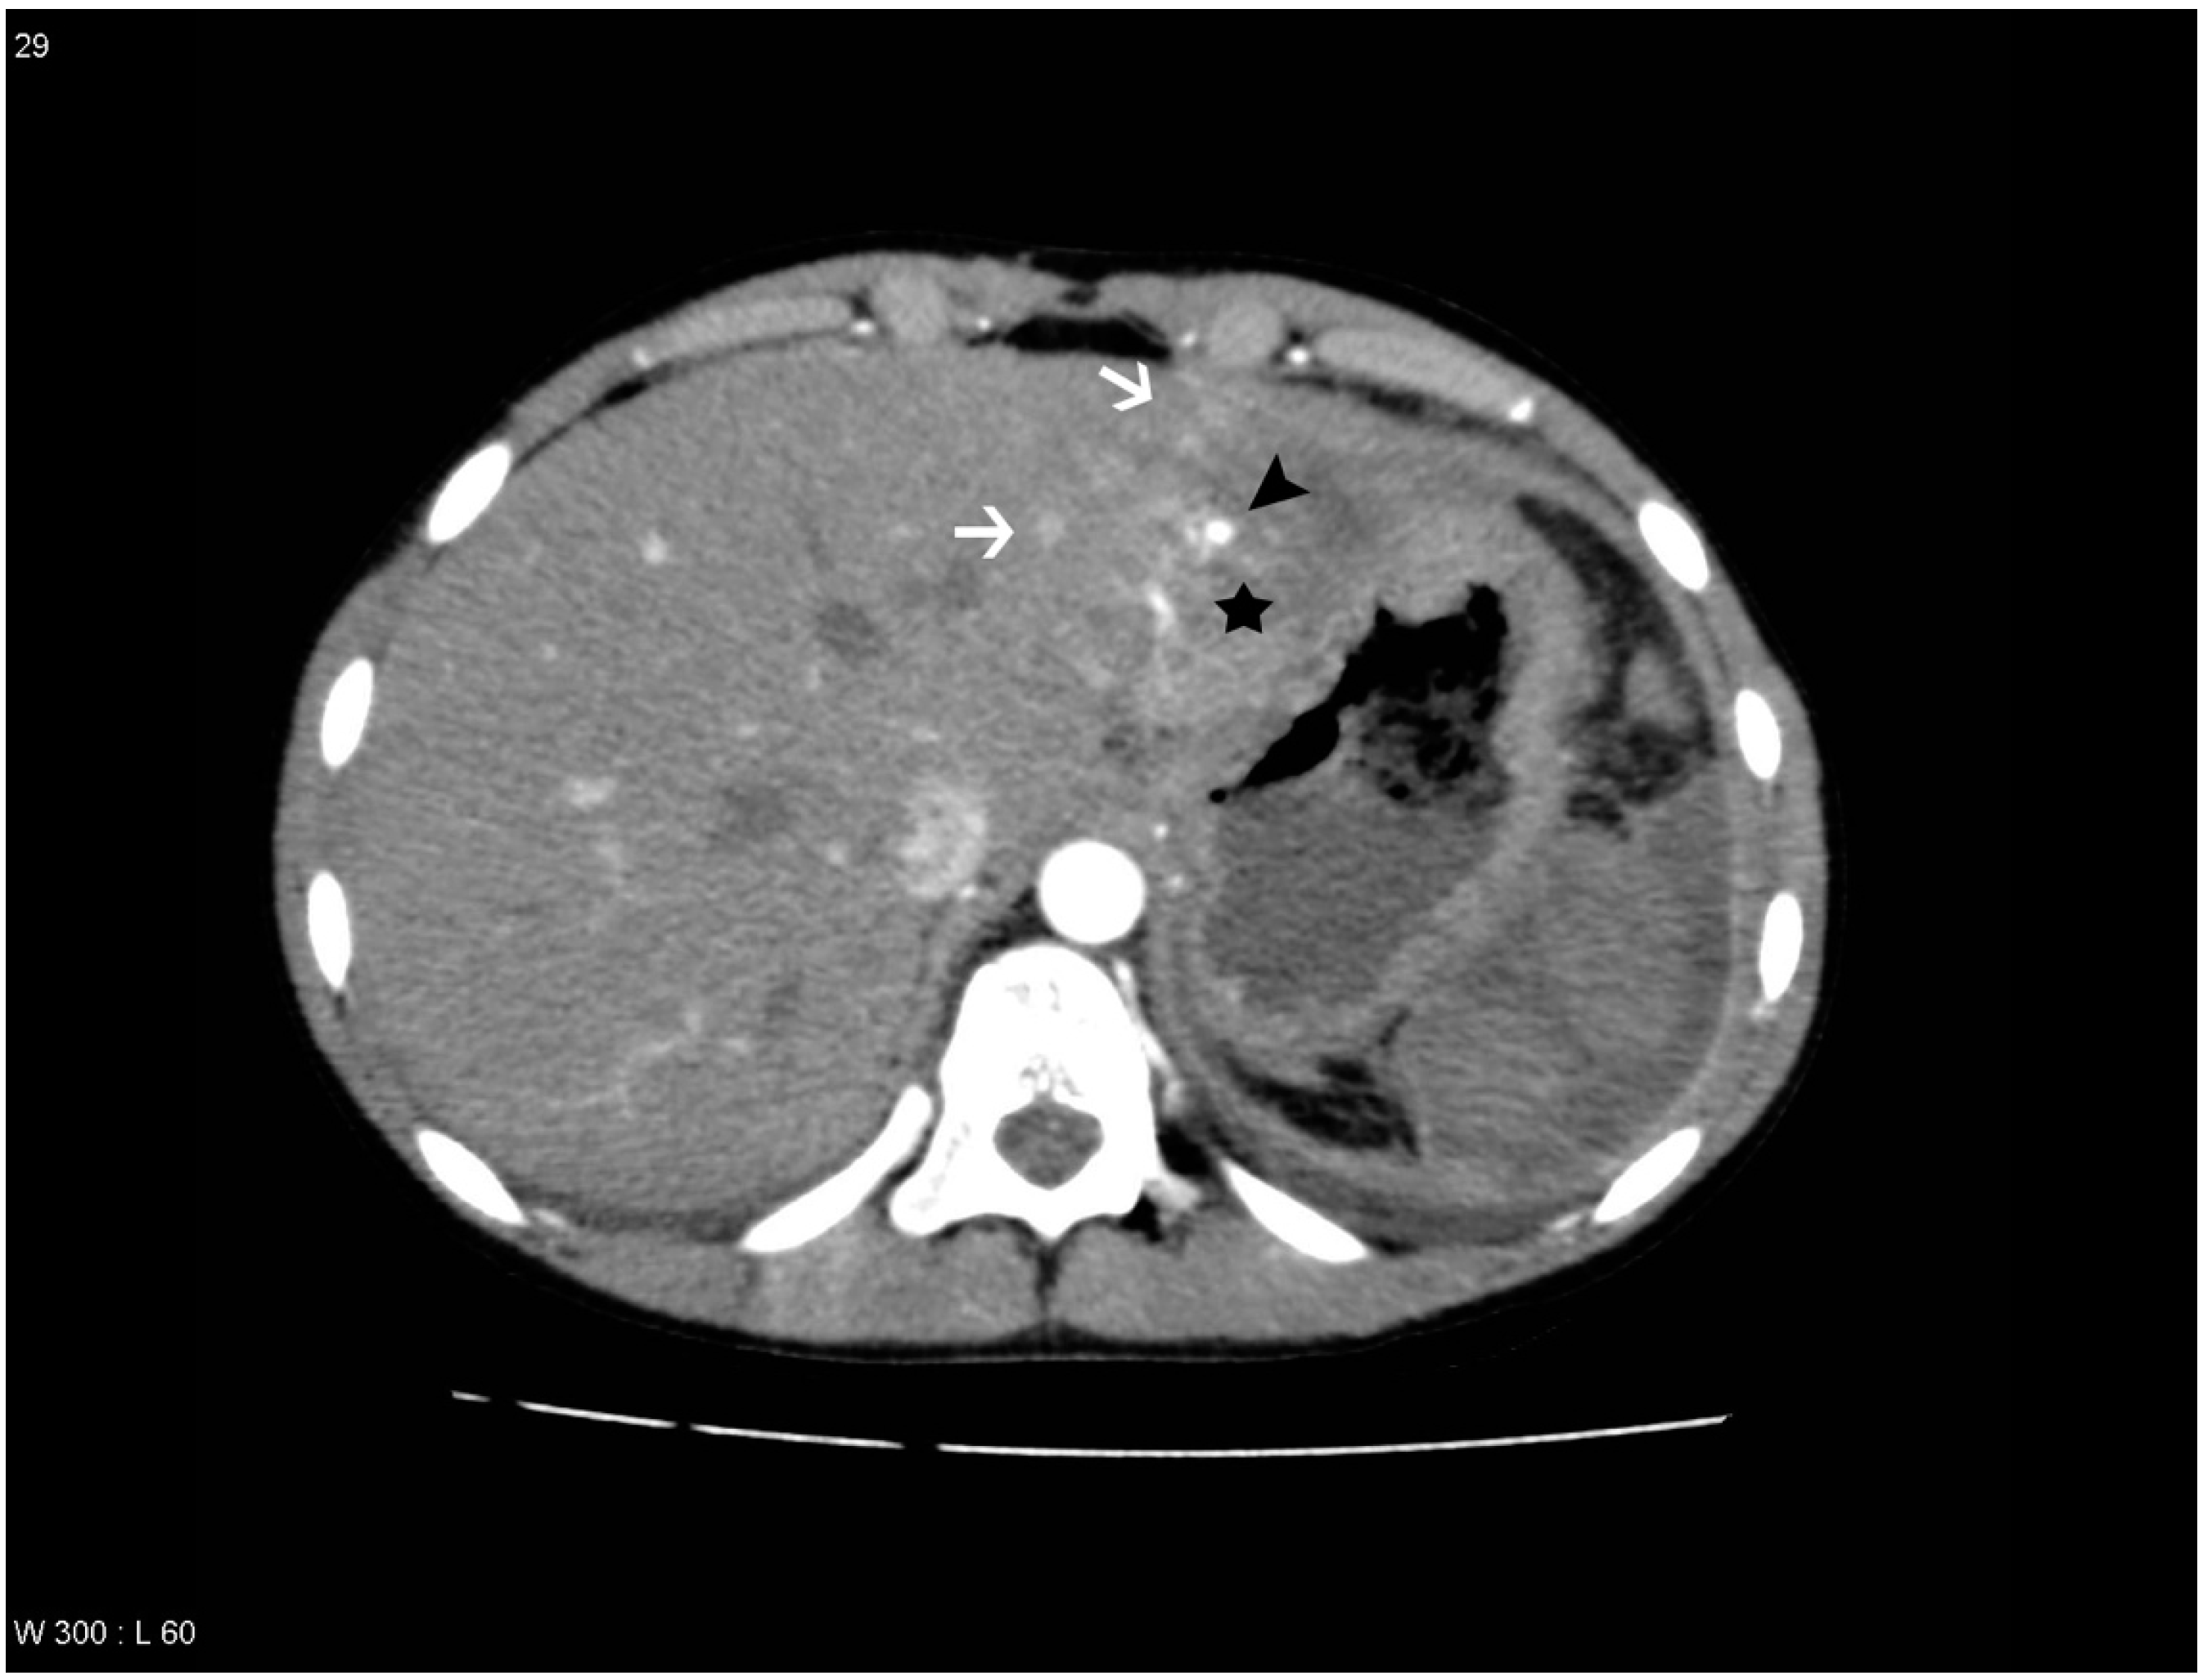

Figure 2. Patient with a liver lesion in segment 4a, 7 and 8. THAD is seen in the periphery of the lesion. PS/AF was not suspected and DSA was not performed. The liver lesion is marked with a black star and the areas with THAD are marked with white arrows.

THAD was defined as an increased arterial enhancement in relation to the liver lesion without resemblance of PS/AF. THAD after liver trauma has previously been described as a localized arterial enhancement with a polymorphous appearance [16,18]. The senior radiologist did not comment on THAD in the initial reading, primarily because THAD is regarded as a benign phenomenon. Therefore, presence of THAD was defined by a consensus between at least two out of three observers (residents in radiology) (Figure 1, Figure 2, Figure 3 and Figure 4).

PS/AF can be recognized and distinguished from THAD by the location, the appearance, and the HU level. PS/AFs seen in 14% of the patients were all oval or round except one, which was linear, and all had focal enhancement with mean HU levels of 170. All PS/AFs were found within the liver lesions (Figure 1 and Figure 4). PS and AF were indistinguishable as stated previously by others [9]. Areas with THAD seen in 54% of the patients had hazy borders, were all found in the periphery of the lesion and with mean HU levels of 100 (Figure 1, Figure 2, Figure 3 and Figure 4).